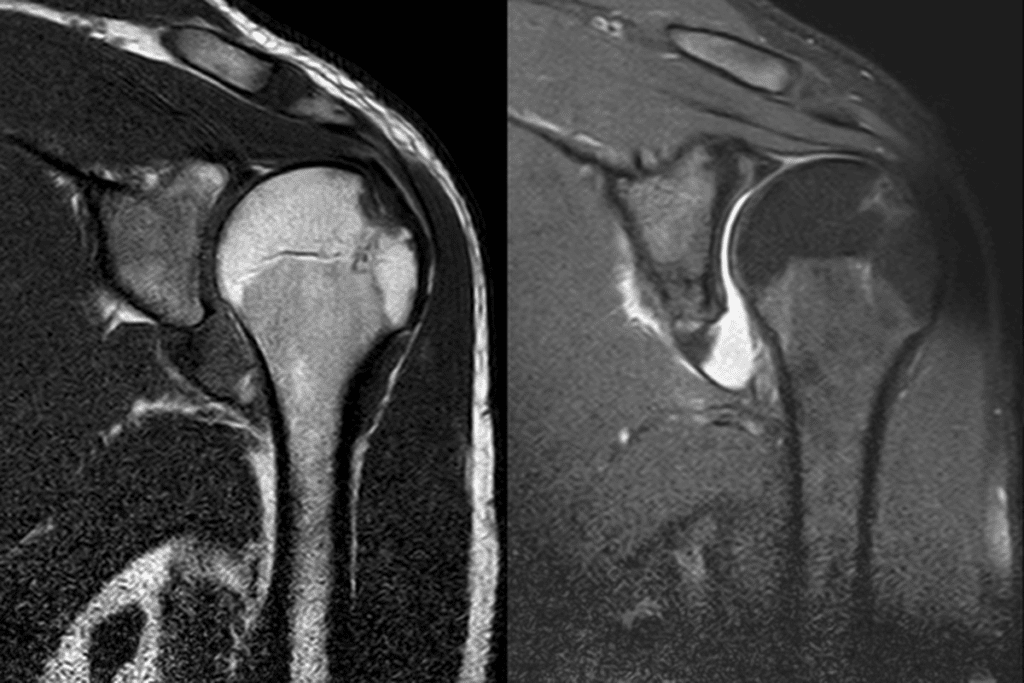

The Role of X-Rays, CT, and MRI

X-rays remain the primary tool for confirming bone displacement. They reveal fractures needing specialized care while guiding anesthesia decisions. “Quick imaging prevents unnecessary movement during joint realignment,” states ER nurse practitioner Alicia Cho.

Magnetic resonance imaging (MRI) excels at showing ligament tears or cartilage damage. These details help doctors adjust pain management timelines. For complex cases involving shattered bones, computed tomography (CT) scans provide 3D views that inform surgical planning.

Which imaging tests diagnose dislocations accurately?

X-rays confirm bone alignment after injury. For soft tissue assessment, MRI scans evaluate ligament tears, while CT scans detect subtle fractures. These tests guide treatment plans for complex cases.